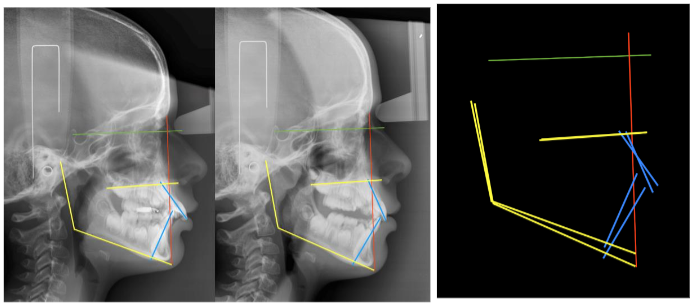

Rivero JC, et al. conducted a comparative cross-sectional study between two groups of patients (N=10) with skeletal class II, with mandibular hypoplasia, age range between 10-14 years. One group was treated with HBO (Herbst Occlusal Rod) and the other with Twin-Block. Cephalometric values were compared between T0 and T1 between both groups, to determine if there were differences in terms of mandibular advancement obtained, proclination of the mandibular incisor, mandibular posterior rotation, etc. After comparing the means with the Student T test, it was concluded that there were no statistically significant differences between the two groups (p > 0.05). HBO achieved greater advancement, but also greater proclination of the lower incisor and greater secondary mandibular posterior rotation.

The clinical procedure consists of taking records of the working models obtained by intraoral scanning of both dental arches, and of the palatal and lingual mucosa. The interocclusal record must be scanned, faithfully respecting the constructive bite in advance, with a flame-heated Godiva (jig). At 2/3 of the maximum clinical advancement.

The manufacturing is customized, to the exact measurement of each patient and each stage of treatment, by thermo-curing, stereolithography, or 3D printing. Regarding clinical management and given that physiologically a posterior and anterior disocclusion occurs between both arches, motivated by the condylar trajectory, following the articular eminences and, because it is closely related to the neuromuscular pattern of each patient (the more brachyfacial, the more posterior disocclusion), we must manage the vertical development of the posterior dentoalveolar processes and the anterior dentoalveolar dimension (incisal) depending on whether we need to intrude or extrude one or the other, at the same time that we will correct the transverse parameters correlating both arches.